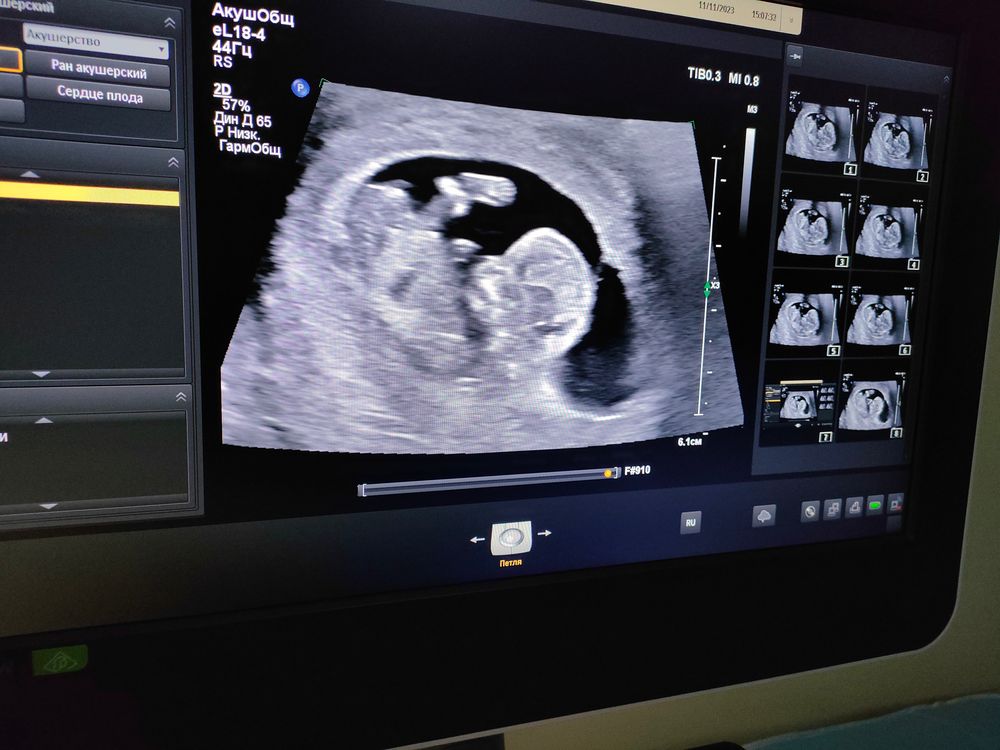

Съездила сегодня на УЗИ бесплатно) хороший УЗИст мужчина посмотрел сказал что все хорошо развивается оказывается там одна быть двойня но развиваться начал один ну главное что с ним все хорошо) даже пол сказал

Тася Гаврикова, да🤭 УЗИст говорит смотри смотрел наверное минут 20-30 прям чётко показал и муж заходит я спрашиваю как думаешь кто он говорит девочка?! УЗИст говорит ага хороший такой как девочка 😂